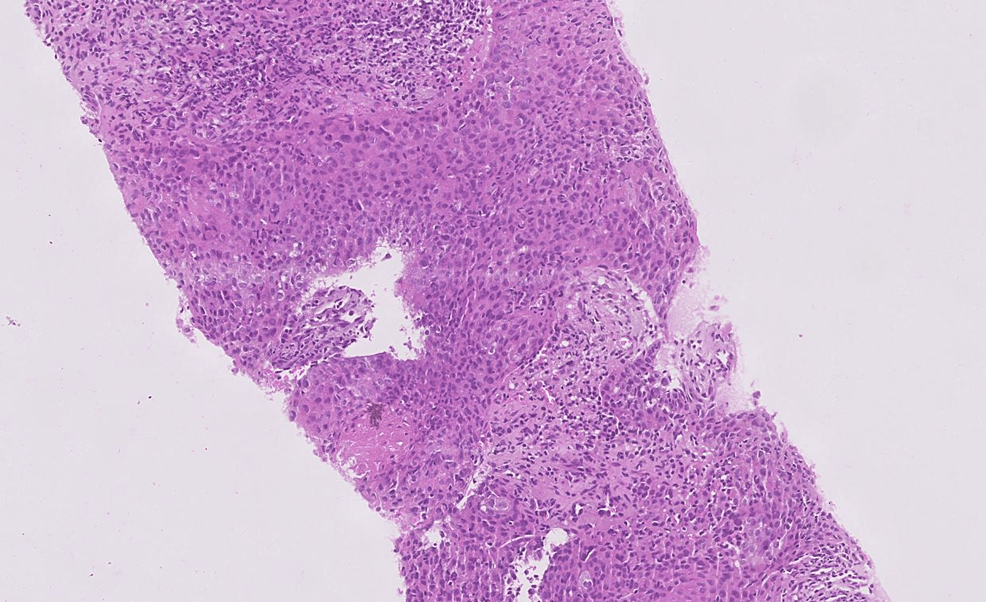

Lymphoepithelial carcinoma (hematoxylineosin) (A) poorly Thymic Lymphoepithelial Carcinoma Thymic epithelial tumors (tets) are rare tumors, including thymoma, thymic carcinoma, and thymic neuroendocrine tumors. Thymic carcinoma (tc) is a rare thymic epithelial neoplasm (ten) with heterogeneous features. In the who 2021 classification, thymic carcinoma includes the following new subtypes (): Thymic lymphoepithelial carcinoma (tlec) is a primary thymic carcinoma that accounts for about 14% of all thymic epithelial tumors. Thymic Lymphoepithelial Carcinoma.

Pathology Outlines Lymphoepithelial carcinoma Thymic Lymphoepithelial Carcinoma Thymic carcinoma (tc) is a rare thymic epithelial neoplasm (ten) with heterogeneous features. The recognition of clinical, radiologic, and. Thymic lymphoepithelial carcinoma (tlec) is a primary thymic carcinoma that accounts for about 14% of all thymic epithelial tumors and is classified into. In the who 2021 classification, thymic carcinoma includes the following new subtypes (): Thymic lymphoepithelial carcinoma (tlec) is. Thymic Lymphoepithelial Carcinoma.

Pathology Outlines Lymphoepithelial carcinoma Thymic Lymphoepithelial Carcinoma Thymic lymphoepithelial carcinoma (tlec) is a primary thymic carcinoma that accounts for about 14% of all thymic epithelial. The recognition of clinical, radiologic, and. In the who 2021 classification, thymic carcinoma includes the following new subtypes (): Thymic lymphoepithelial carcinoma (tlec) is a primary thymic carcinoma that accounts for about 14% of all thymic epithelial tumors and is classified into.. Thymic Lymphoepithelial Carcinoma.